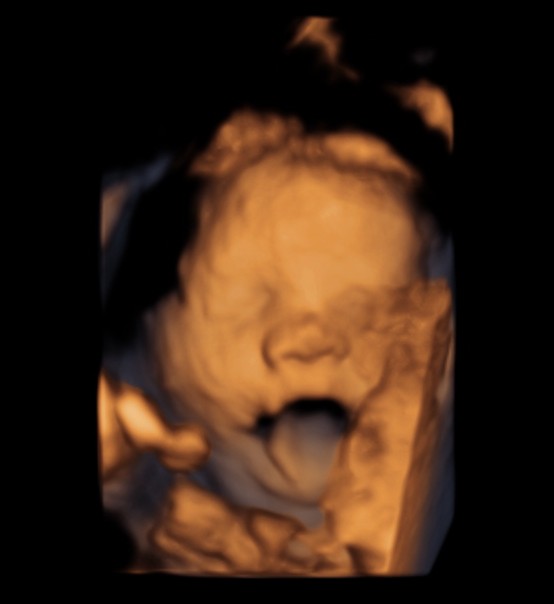

BABY FACE ( Just for fun ) Date: May 25, 2014Author: kriznan Category: 3 d images, fetal face, Fetal Ultrasound, ultrasound images Tags: baby face 3 d images, baby sucking finger, baby yawning Post navigation ← HEMANGIOMA OF THE LIVER IUGR OR SKELETAL DYSPLASIA OR RENAL DYSPLASIA → This is just an intermediate filler . enjoy the expressions. Thinking Yawning or just putting out the tongue Sucking the fingers Wondering So , what is lost now ? ok Papparazi ! enough for the day . go away. Share this: Share on X (Opens in new window) X Share on Facebook (Opens in new window) Facebook Email a link to a friend (Opens in new window) Email Share on LinkedIn (Opens in new window) LinkedIn Share on WhatsApp (Opens in new window) WhatsApp More Print (Opens in new window) Print Share on Reddit (Opens in new window) Reddit Share on Tumblr (Opens in new window) Tumblr Share on Pinterest (Opens in new window) Pinterest Share on Telegram (Opens in new window) Telegram Like Loading...